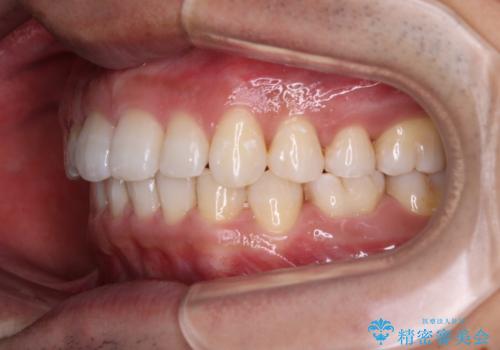

- 前歯の隙間を気にして来院された患者様です。

下顎前歯が見えなくなるくらいに深い咬み合わせであり、さらに上顎の正中が開くほど下の前歯が突き上げている状態でした。

奥歯は手前に倒れてしまっているため、後方に起き上がらせることで深い咬み合わせ・ディープバイトを改善する必要があります。

ディープバイトの方は項合力が強大であることが特徴のため、仕上がりを重要視して、ワイヤー装置にて矯正治療を行うこととしました。